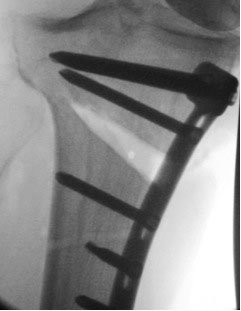

The operation involves cutting the shin bone (tibia) just below the knee joint via either the opening wedge or closing wedge techniques that I went though in Part 1e of this course. The image on the right of an opening wedge high tibial osteotomy fixed with the Tomofix plate is reproduced with the permission of Synthes.

The gap in this film shows up pale and the plate is dark. Usually in an X-ray it is the other way around, but the shades here have been reversed.